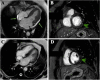

Case presentation: A 46-year-old woman without previous comorbidities with a 1-day history of symptoms tested positive for ZIKV by real time reverse transcriptase polymerase chain reaction (rRT-PCR). She was admitted two days after with clinical worsening, cardiac enzymes elevated, and cardiac imaging findings, and the diagnosis of myopericarditis was made. The patient was treated and presented significant clinical improvement after one year.